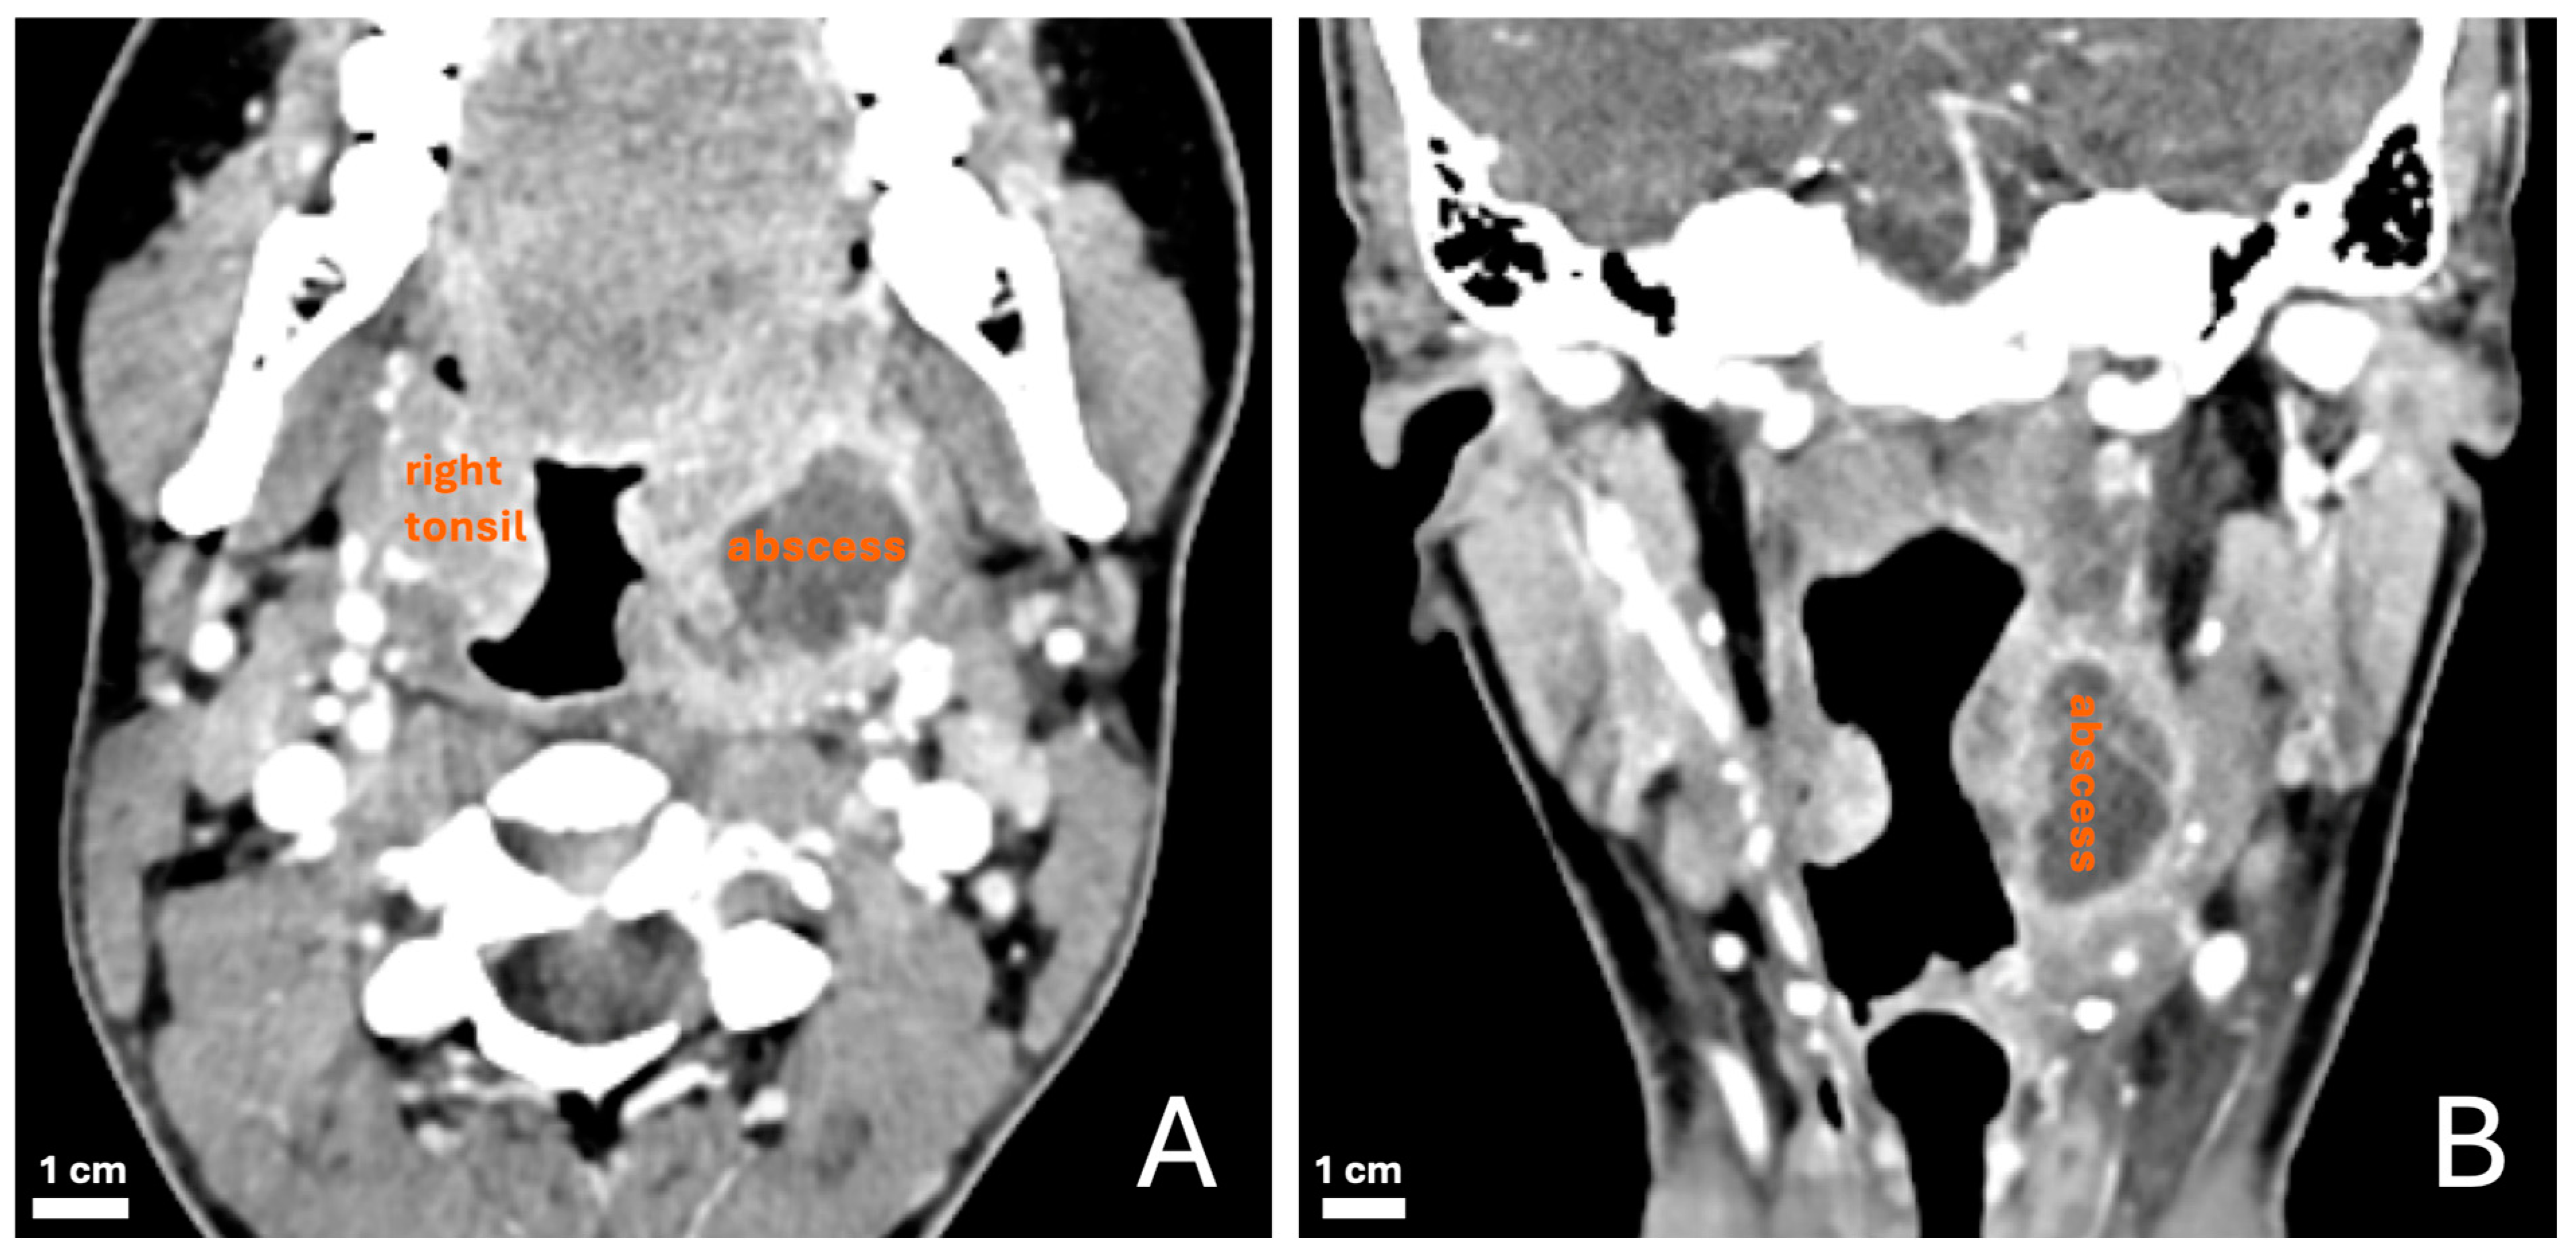

2.3. Study Protocol, Clinical Evaluation and CT Criteria, and Standard of Reference